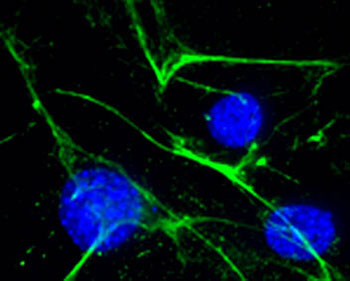

Dr. Mead is a trained developmental and molecular biologist with a keen focus on cardiovascular development and disease. His research centers on how changes in the extracellular matrix results in dysfunctional heart development and resulting congenital heart defects. Dr. Mead utilizes mouse models of congenital heart disease, biochemistry and proteomics to understand the molecular mechanisms underlying these diseases towards the development of therapeutic approaches. His current research focus is on the novel concept of inhibiting a protease that remodels fibrillin microfibrils in the aorta in an effort to identify a therapeutic for Marfan syndrome.